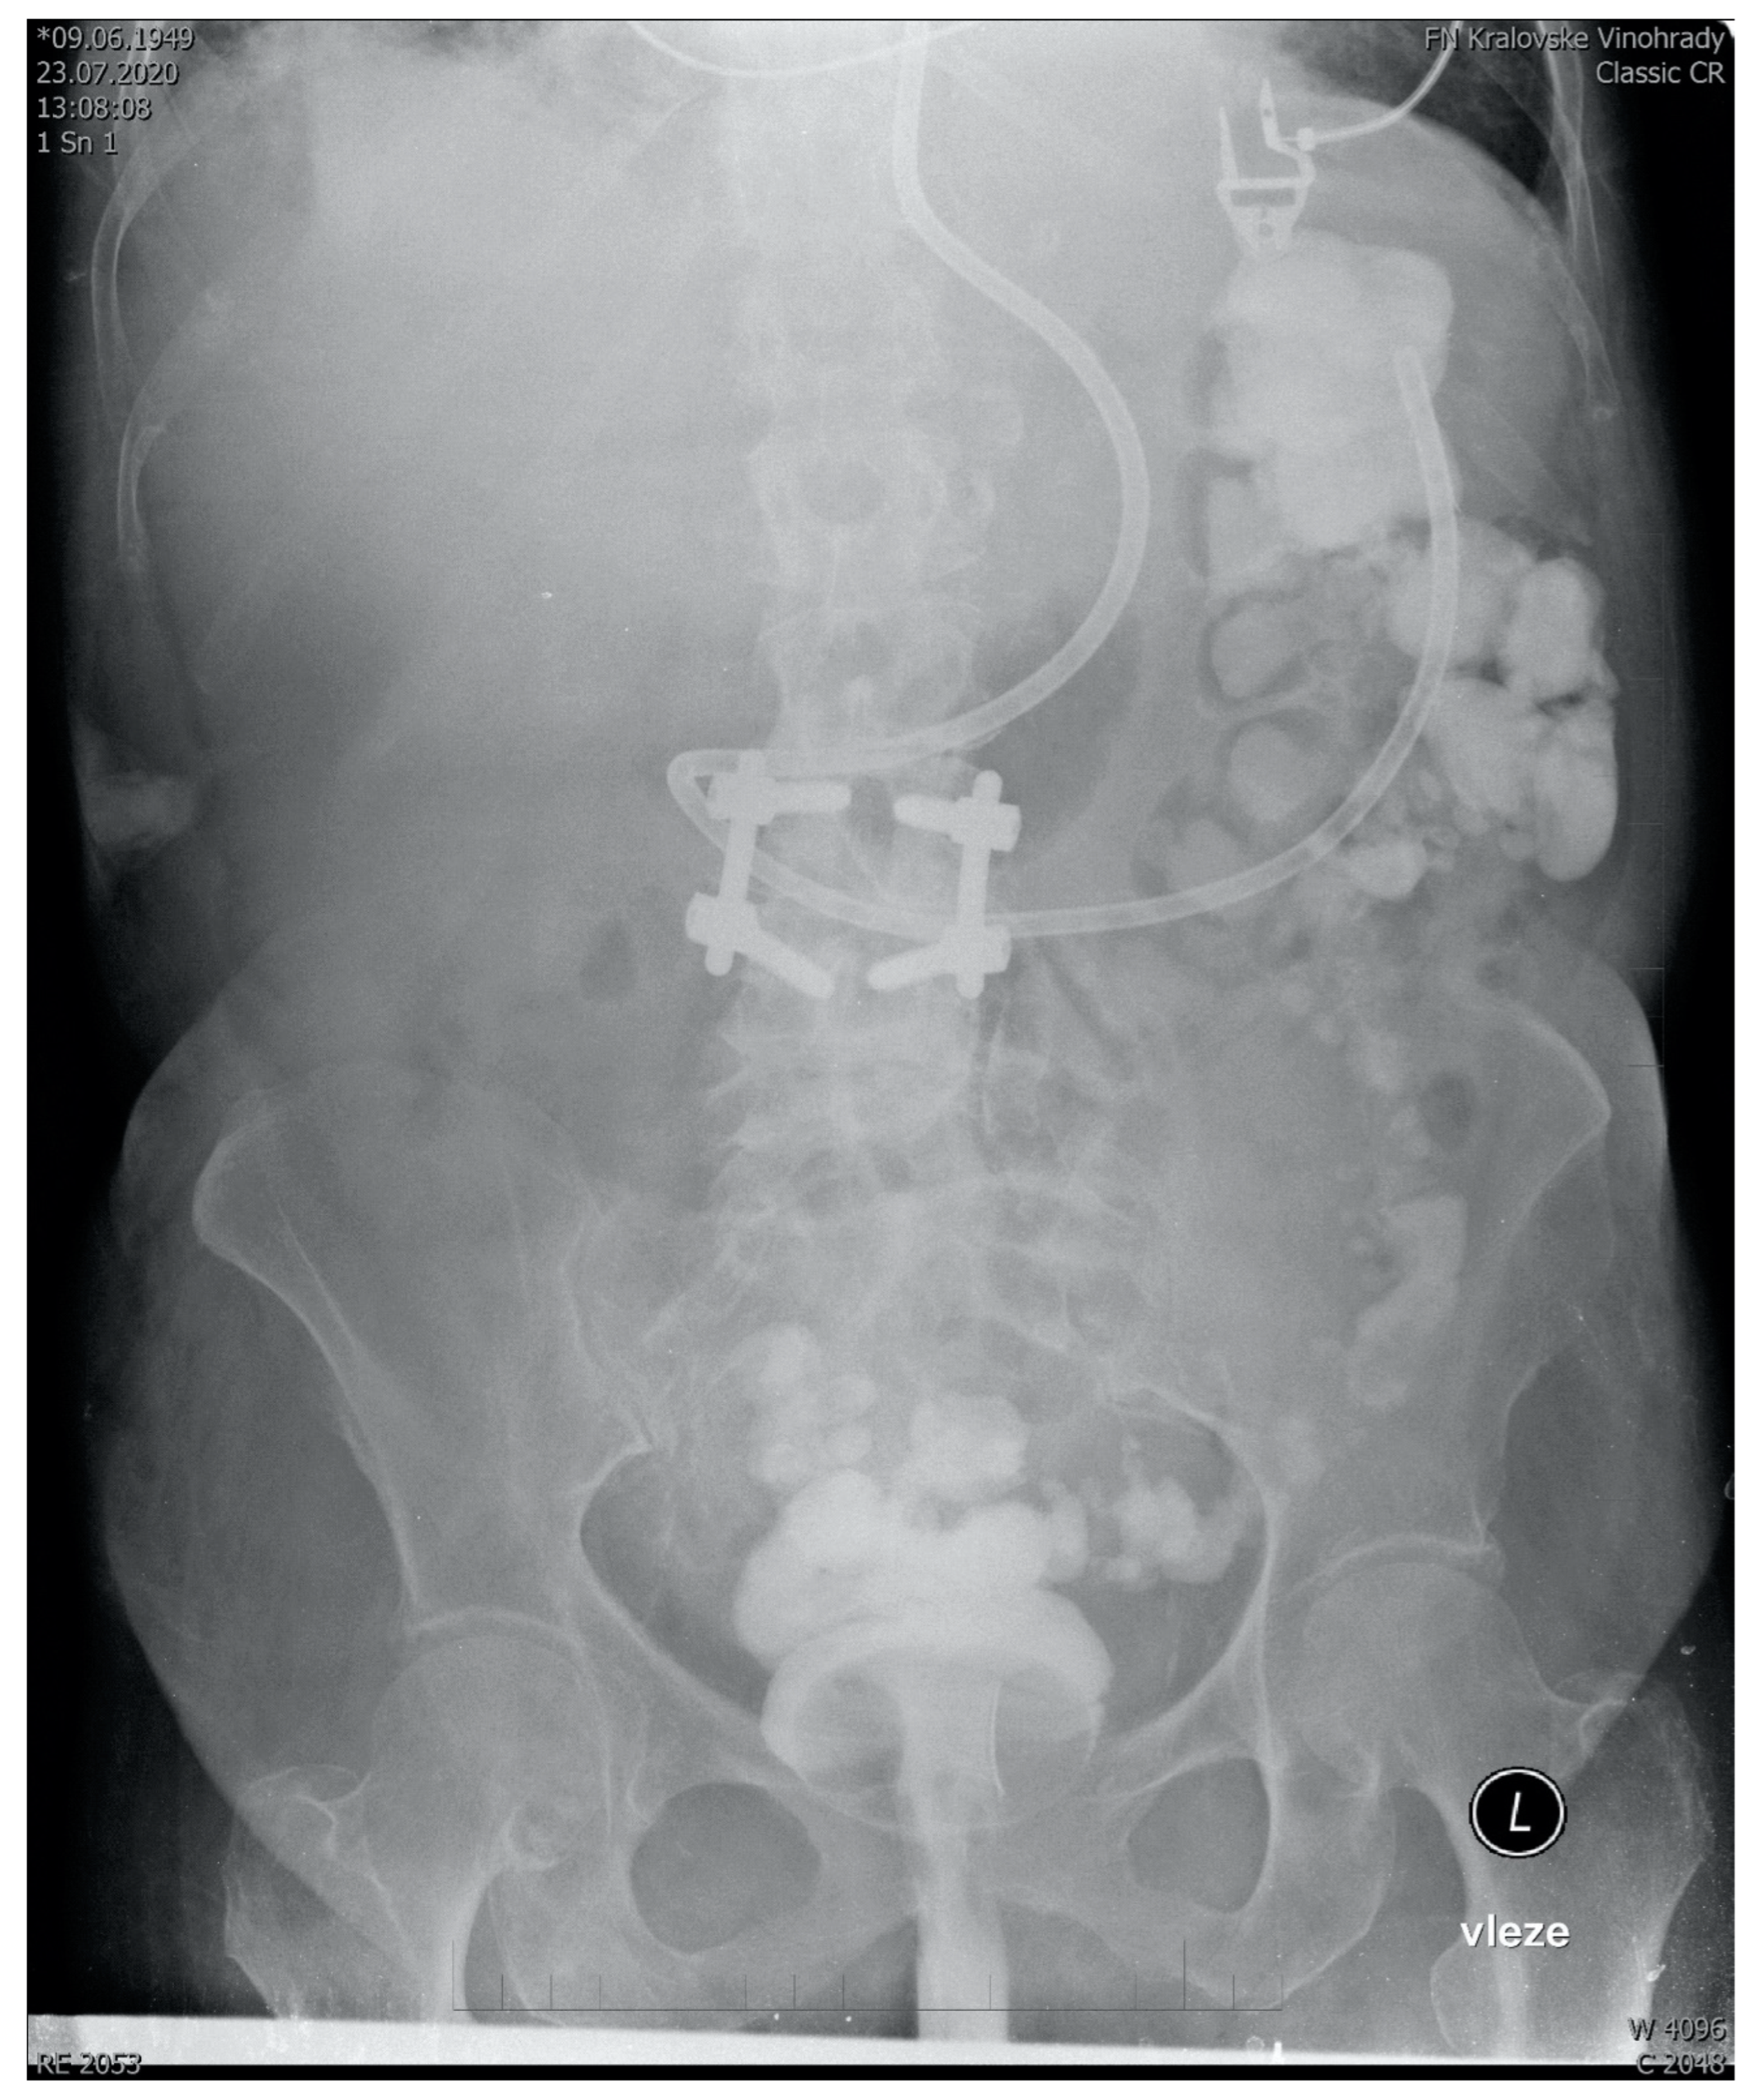

The full text of SOPs can be found in Supplementary Materials. There we describe the development of a standard operating procedure for multi-donor fecal microbial transplantation in critically ill patients, starting from donor selection and finishing with post-procedure recipient care. In summary, our SOP recommends the use of a multi-donor transplant consisting of seven 50 mL aliquots from seven donors. The aliquots are prepared from healthy unrelated volunteers, who regularly donate. In addition to standard guidelines-driven [57,58,59] precautions and tests (See Supplementary Digital Content) in donors to prevent transmissible infection, the deep-frozen transplant mixed with glycerol is quarantined for at least 2 months before use. The transplantation itself is performed by a semi-rigid rectal irrigation tube in a patient positioned to the left semi lateral Trendelenburg’s position for 15 min and then in the right semi lateral Trendelenburg’s position for another 15 min. This ensures the distribution of the transplant well throughout the length of the colon (Figure 1). This recommendation has been developed as a modification of existing guidelines for the use of FMT to eradicate Clostridioides difficile in other than intensive care settings [60,61]. All modifications and their justifications are described below.

Figure 1.

Abdominal X-ray showing the spread of 350 mL transplant mixed with 5 mL of contrast agent 15 min after administration to a sedated ventilated patient via semirigid rectal tube. Fecal derivation system (Flexiseal©) has been clamped immediately after administration with the rectal balloon inflated being clearly visible on the image. Note: The addition of a contrast agent is normally not a part of FMT and it should be noticed that there are no robust data on how FMT without contrast agent spreads after rectal administration.

With regards to the way of administration, various methods were considered. The lower GI or “Southern” route (via colonoscopy or retention enema) has been found more efficient in microbiome restoration compared to the upper GI “Nothern” routes (esophagogastroduodenoscopy, nasogastric, nasojejunal tube, poop pills) [70]. Additionally, we considered upper GI administration of fecal material into the small intestine with a potentially disrupted epithelial barrier too risky. Of particular concern, was aspiration, a recognized complication of the upper GI route [71]. Moreover, in a survey, the majority of ICU nurses considered the administration of fecal material into the colon more acceptable for them as opposed to nasogastric administration (Iva Havirova thesis, unpublished). Given the logistic issues with the availability of endoscopists and considerable risks of endoscopy [72], we have chosen administration by an enema, despite its lower efficiency, compared to colonoscopy. With appropriate patient positioning, we found graft distribution throughout the colon acceptable, reaching the ascendent colon (Figure 1). Indeed, this case-based anecdotal data are far from conclusive with regards to FMT spread and effect size. To maximize engraftment, we recommend performing FMT no sooner than 48 h after the last dose of antibiotics. An important objective of the upcoming trials should not only be to provide more data on the distribution of the graft in the recipient’s colon, but also to test the efficacy of donor microbiome engraftment.